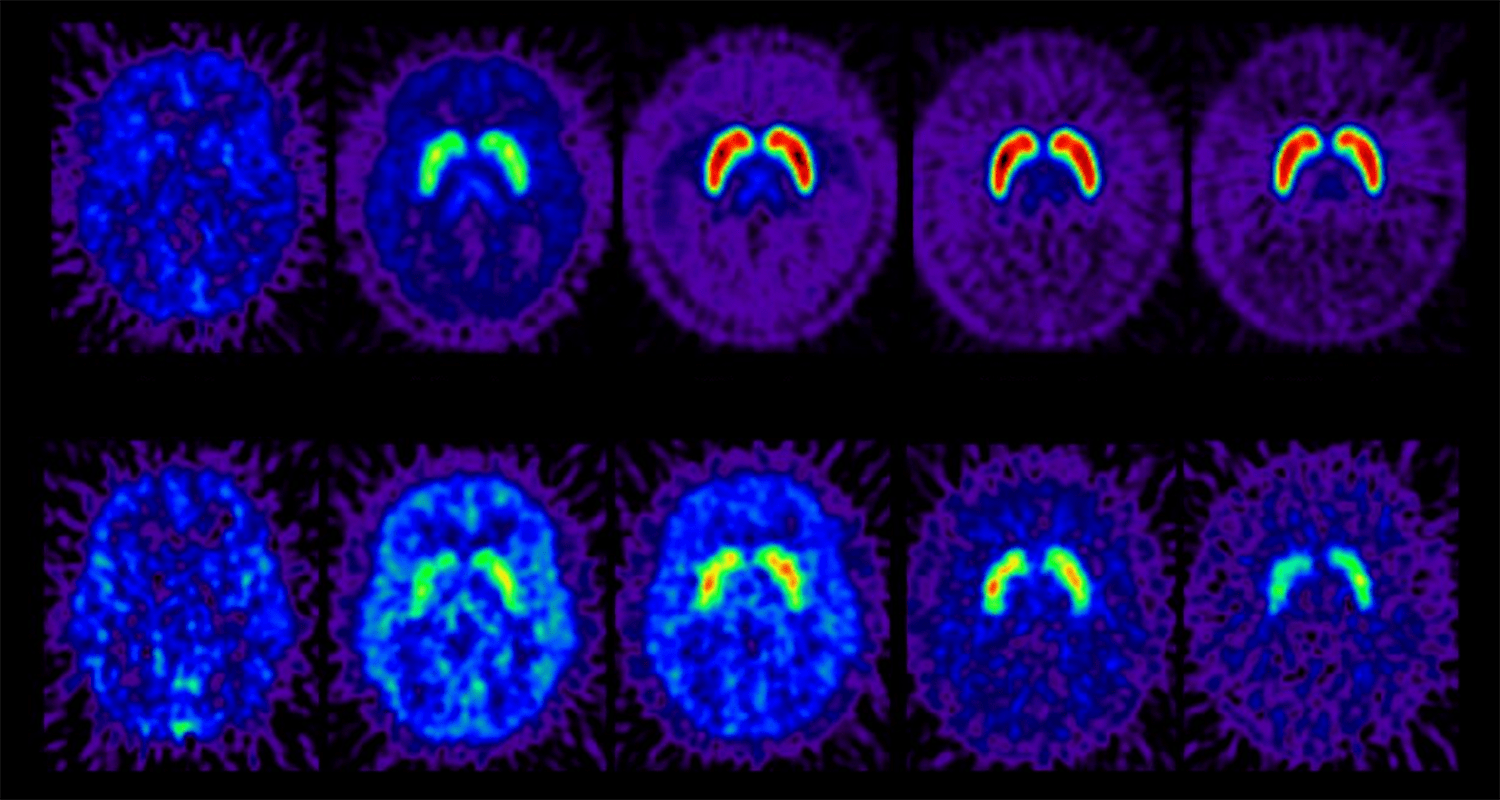

IU researchers find electroacupuncture releases stem cells to relieve pain, promote tissue repair

The researchers performed a series of lab tests involving humans, horses and rodents that follow the effects of electroacupuncture from the stimulus of the needle all the way to the brain, resulting in the release of reparative mesenchymal stem cells (MSCs) into the bloodstream.